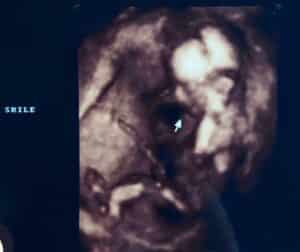

Our son, Jackson, will be here in March of 2023!

This is proof that all you need is one functioning tube!